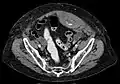

Rectus sheath hematoma seen on axial CT – with active bleeding under Marcoumar- Rectus sheath hematoma as seen on ultrasound[5]